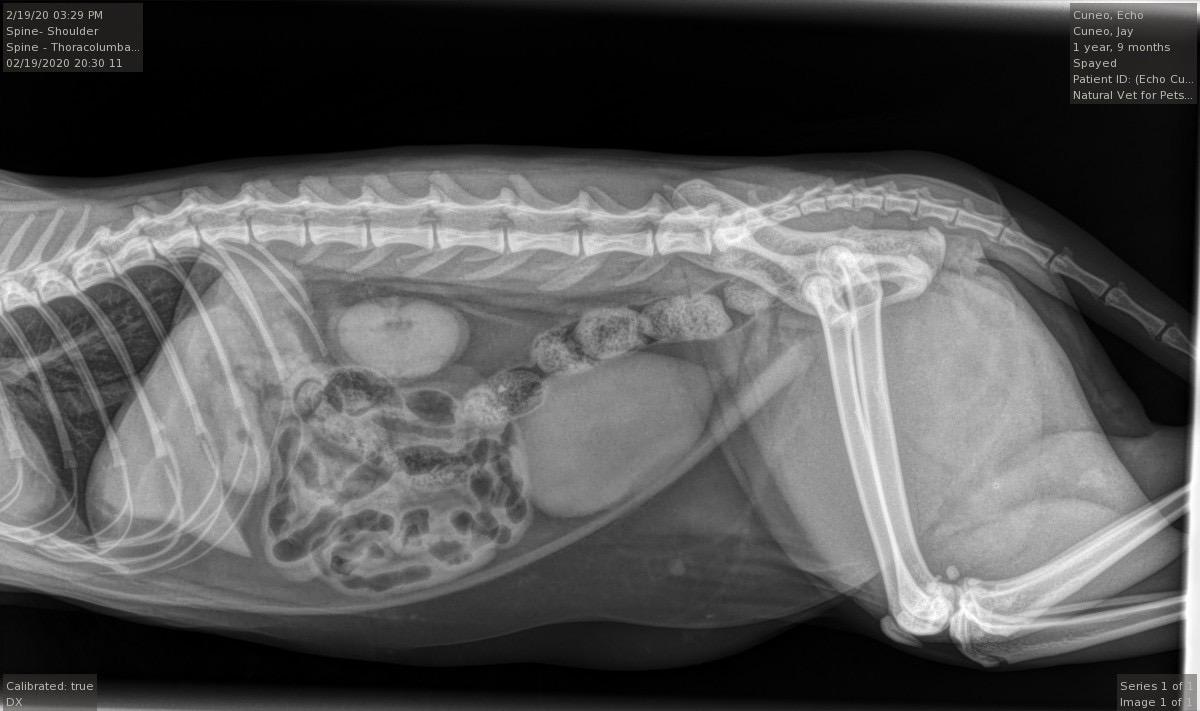

Pet's info: Cat | Mixed Breed | Female | spayed | 1 year and 10 months old | 9.5 lbs

My cat seemed to hurt her leg somehow this morning and was growling/hissing/didn’t want food. Vet sedated her to X-ray/examine. Said nothing broken and felt alright she may have just sprained. She has buprenorphine for pain next few days. Do her x rays indeed look normal and ok from what can be seen in X-ray? No swelling, but definitely still painful as initial drugs wore off at home. Just gave tonight’s oral buprenorphine dose

Hi, there is no evidence of any fractures on the pictures of these X-rays. Is Echo on any antinflammatories ? I often find cat bites can be painful even when superficial, is Echo allowed outside ? As this is all recent, it is likely that you need to give Echo some time to get better. Within 3-4 days with rest, pain relief she should go back to her normal self. If Buprenorphine is helping but just for a short period of time, I would enquire about having additional pain relief in terms of antinflammatories . This is provided that Echo is otherways healthy and does not have any other health concerns. Hope she gets better soon !